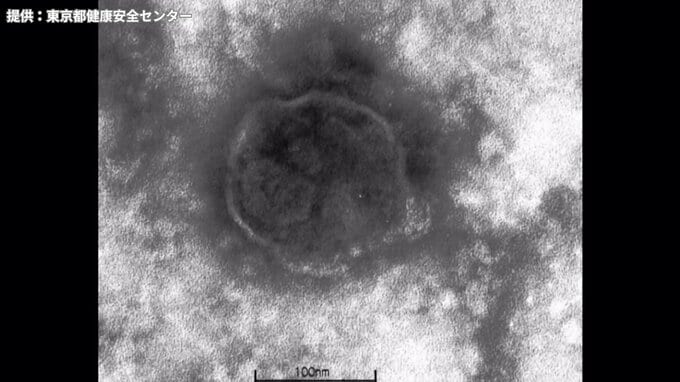

Q.そもそもはしかとはどんな病気?

「はしかウイルスってウイルスによって起こる病気ですけれども、伝染力が非常に強いのと、あと結構やっぱり重い病気です」「日本の健康な子供さんでも300人から1000人に1人は亡くなる恐れがありますし、大人の方がもしかかると、子供以上に重症化することがあります」